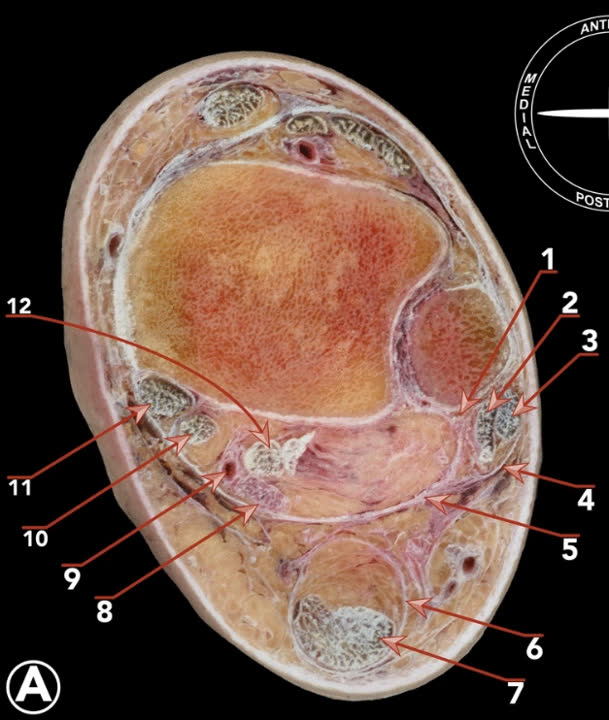

Костная анатомия дистального отдела большеберцовой кости

Суставная поверхность дистального отдела большеберцовой кости (плафон) имеет вогнутую форму в сагиттальной плоскости, что обеспечивает конгруэнтность с блоком таранной кости. Площадь суставной поверхности плафона составляет примерно 10 см². Передний край плафона (margo anterior, передний бугорок Chaput/Tillaux-Chaput) выступает дистальнее заднего, формируя переднюю «губу», ограничивающую тыльное сгибание. Задний край (задняя лодыжка, фрагмент Volkmann) образует заднюю опору суставной поверхности и место прикрепления задней порции межберцового синдесмоза.

Медиальная лодыжка является продолжением медиальной колонны и местом прикрепления дельтовидной связки. Вырезка малоберцовой кости (incisura fibularis) расположена на латеральной поверхности дистального отдела большеберцовой кости и формирует ложе для дистального межберцового синдесмоза.

Метафиз большеберцовой кости имеет тонкий кортикальный слой и губчатую структуру, что определяет характерный паттерн разрушения при осевой нагрузке: вдавливание блока таранной кости в плафон с формированием импакции центральной зоны и расщеплением периферических фрагментов.

Мягкотканный покров

Передняя и медиальная поверхности дистального отдела большеберцовой кости покрыты минимальным слоем мягких тканей — кость расположена непосредственно под кожей и подкожной клетчаткой без мышечного покрытия. Это ключевая особенность, определяющая высокую частоту раневых осложнений: отсутствие мышечного буфера делает кожу уязвимой к повреждению при отёке, а закрытие раны при некрозе кожных краёв невозможно без пластических методов.

Латеральная и задняя поверхности покрыты мышцами (малоберцовые, задняя группа голени), что обеспечивает лучшее кровоснабжение и заживление ран. Это одна из причин, по которой задние доступы ассоциированы с меньшей частотой раневых осложнений.

Кровоснабжение и ангиосомы

Дистальный отдел голени кровоснабжается тремя основными артериями, каждая из которых формирует свой ангиосом:

- Передняя большеберцовая артерия — передняя поверхность голеностопного сустава, тыл стопы. Проходит в переднем компартменте между передней большеберцовой мышцей и длинным разгибателем пальцев, затем переходит на тыл стопы как тыльная артерия стопы

- Задняя большеберцовая артерия — медиальная и подошвенная поверхность. Проходит в глубоком заднем компартменте позади медиальной лодыжки

- Малоберцовая артерия — латеральная и задняя поверхность. Конечные ветви (прободающая передняя, латеральная пяточная) кровоснабжают латеральную область голеностопного сустава

Между ангиосомами располагаются «водоразделы» (watershed zones) — зоны двойного кровоснабжения из смежных ангиосом. Параллельные разрезы, расположенные в пределах одного ангиосома, безопаснее, чем разрезы, пересекающие ангиосомные границы.

Передняя поверхность большеберцовой кости — наиболее уязвимая зона из-за минимального мышечного покрытия и конечных ветвей кровоснабжения.

Топография хирургических коридоров

Переднелатеральный коридор (по латеральному краю длинного разгибателя пальцев и передним краем малоберцовой кости): риск повреждения поверхностного малоберцового нерва, который расположен в поверхностном слое до фасции голени. Сосудисто-нервный пучок (a. tibialis anterior, n. peroneus profundus) располагается в глубоком слое, на уровне голеностопного сустава, между сухожилием длинного сгибателя первого пальца и длинным сгибателем пальцев.

Переднемедиальный коридор (между сухожилием передней большеберцовой мышцы и медиальной лодыжкой): должна выполняться минимальная диссекция мягких тканей. Риск повреждения v. saphena magna и n. saphenus, располагающихся впереди медиальной лодыжки в поверхностном слое.

Заднелатеральный коридор (между малоберцовыми мышцами и длинным сгибателем большого пальца): безопасная зона при условии работы латеральнее длинного сгибателя первого пальца (FHL). Риск — n. suralis при мобилизации малоберцовых мышц. Глубокий сосудисто-нервный пучок (a. tibialis posterior, n. tibialis) располагается медиальнее сухожилия длинного сгибателя первого пальца.

Заднемедиальный коридор (между задней большеберцовой мышцей и длинным сгибателем пальцев): обеспечивает доступ к заднемедиальным фрагментам и тарзальному каналу. Риск — задний сосудисто-нервный пучок располагается латеральнее этого интервала.